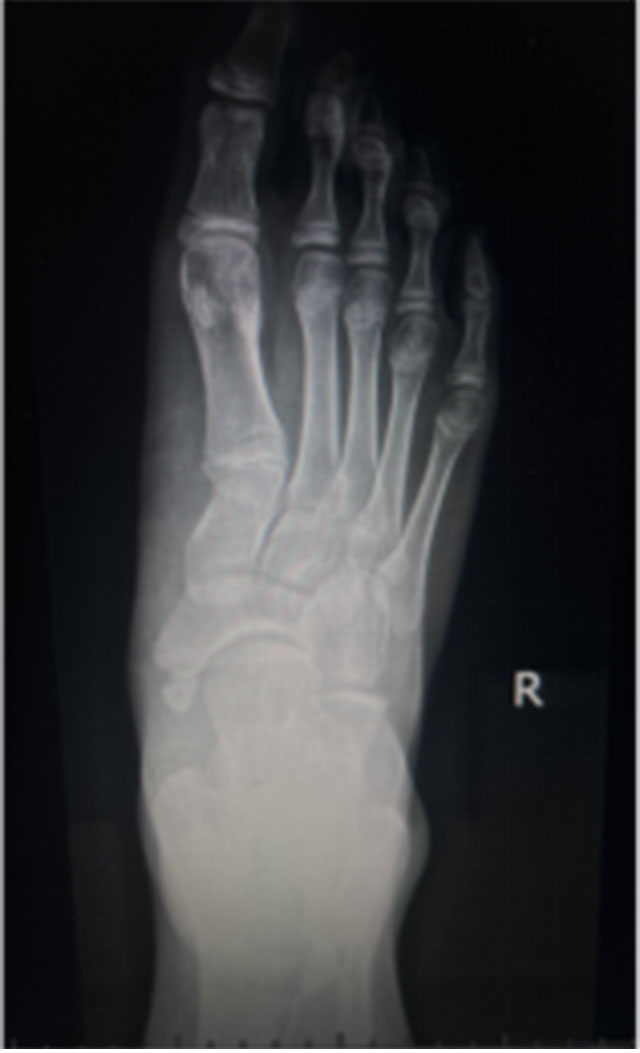

2024年6月13日,西南医科大学附属中医医院骨伤科关节·足踝组张磊博士门诊接诊了一名扁平足的初中生。14岁的小莉走路过程中足底有疼痛感,长时间走路后会感觉足底肿胀,遂来医院就诊,被诊断为“右足副舟骨痛+右足扁平足”,张磊博士团队考虑小莉实际情况,经微创治疗距下关节制动术后,小莉疼痛症状缓解。

12月1日,小莉再次来到骨伤科关节·足踝组复查,外观可见扁平足改善效果明显。

部分青少年患者可选择放入距下关节制动器,改善距下关节活动,缓解疼痛,一定程度改善足的外观及畸形。可联合进行副舟骨切除和胫后肌腱止点重建术。